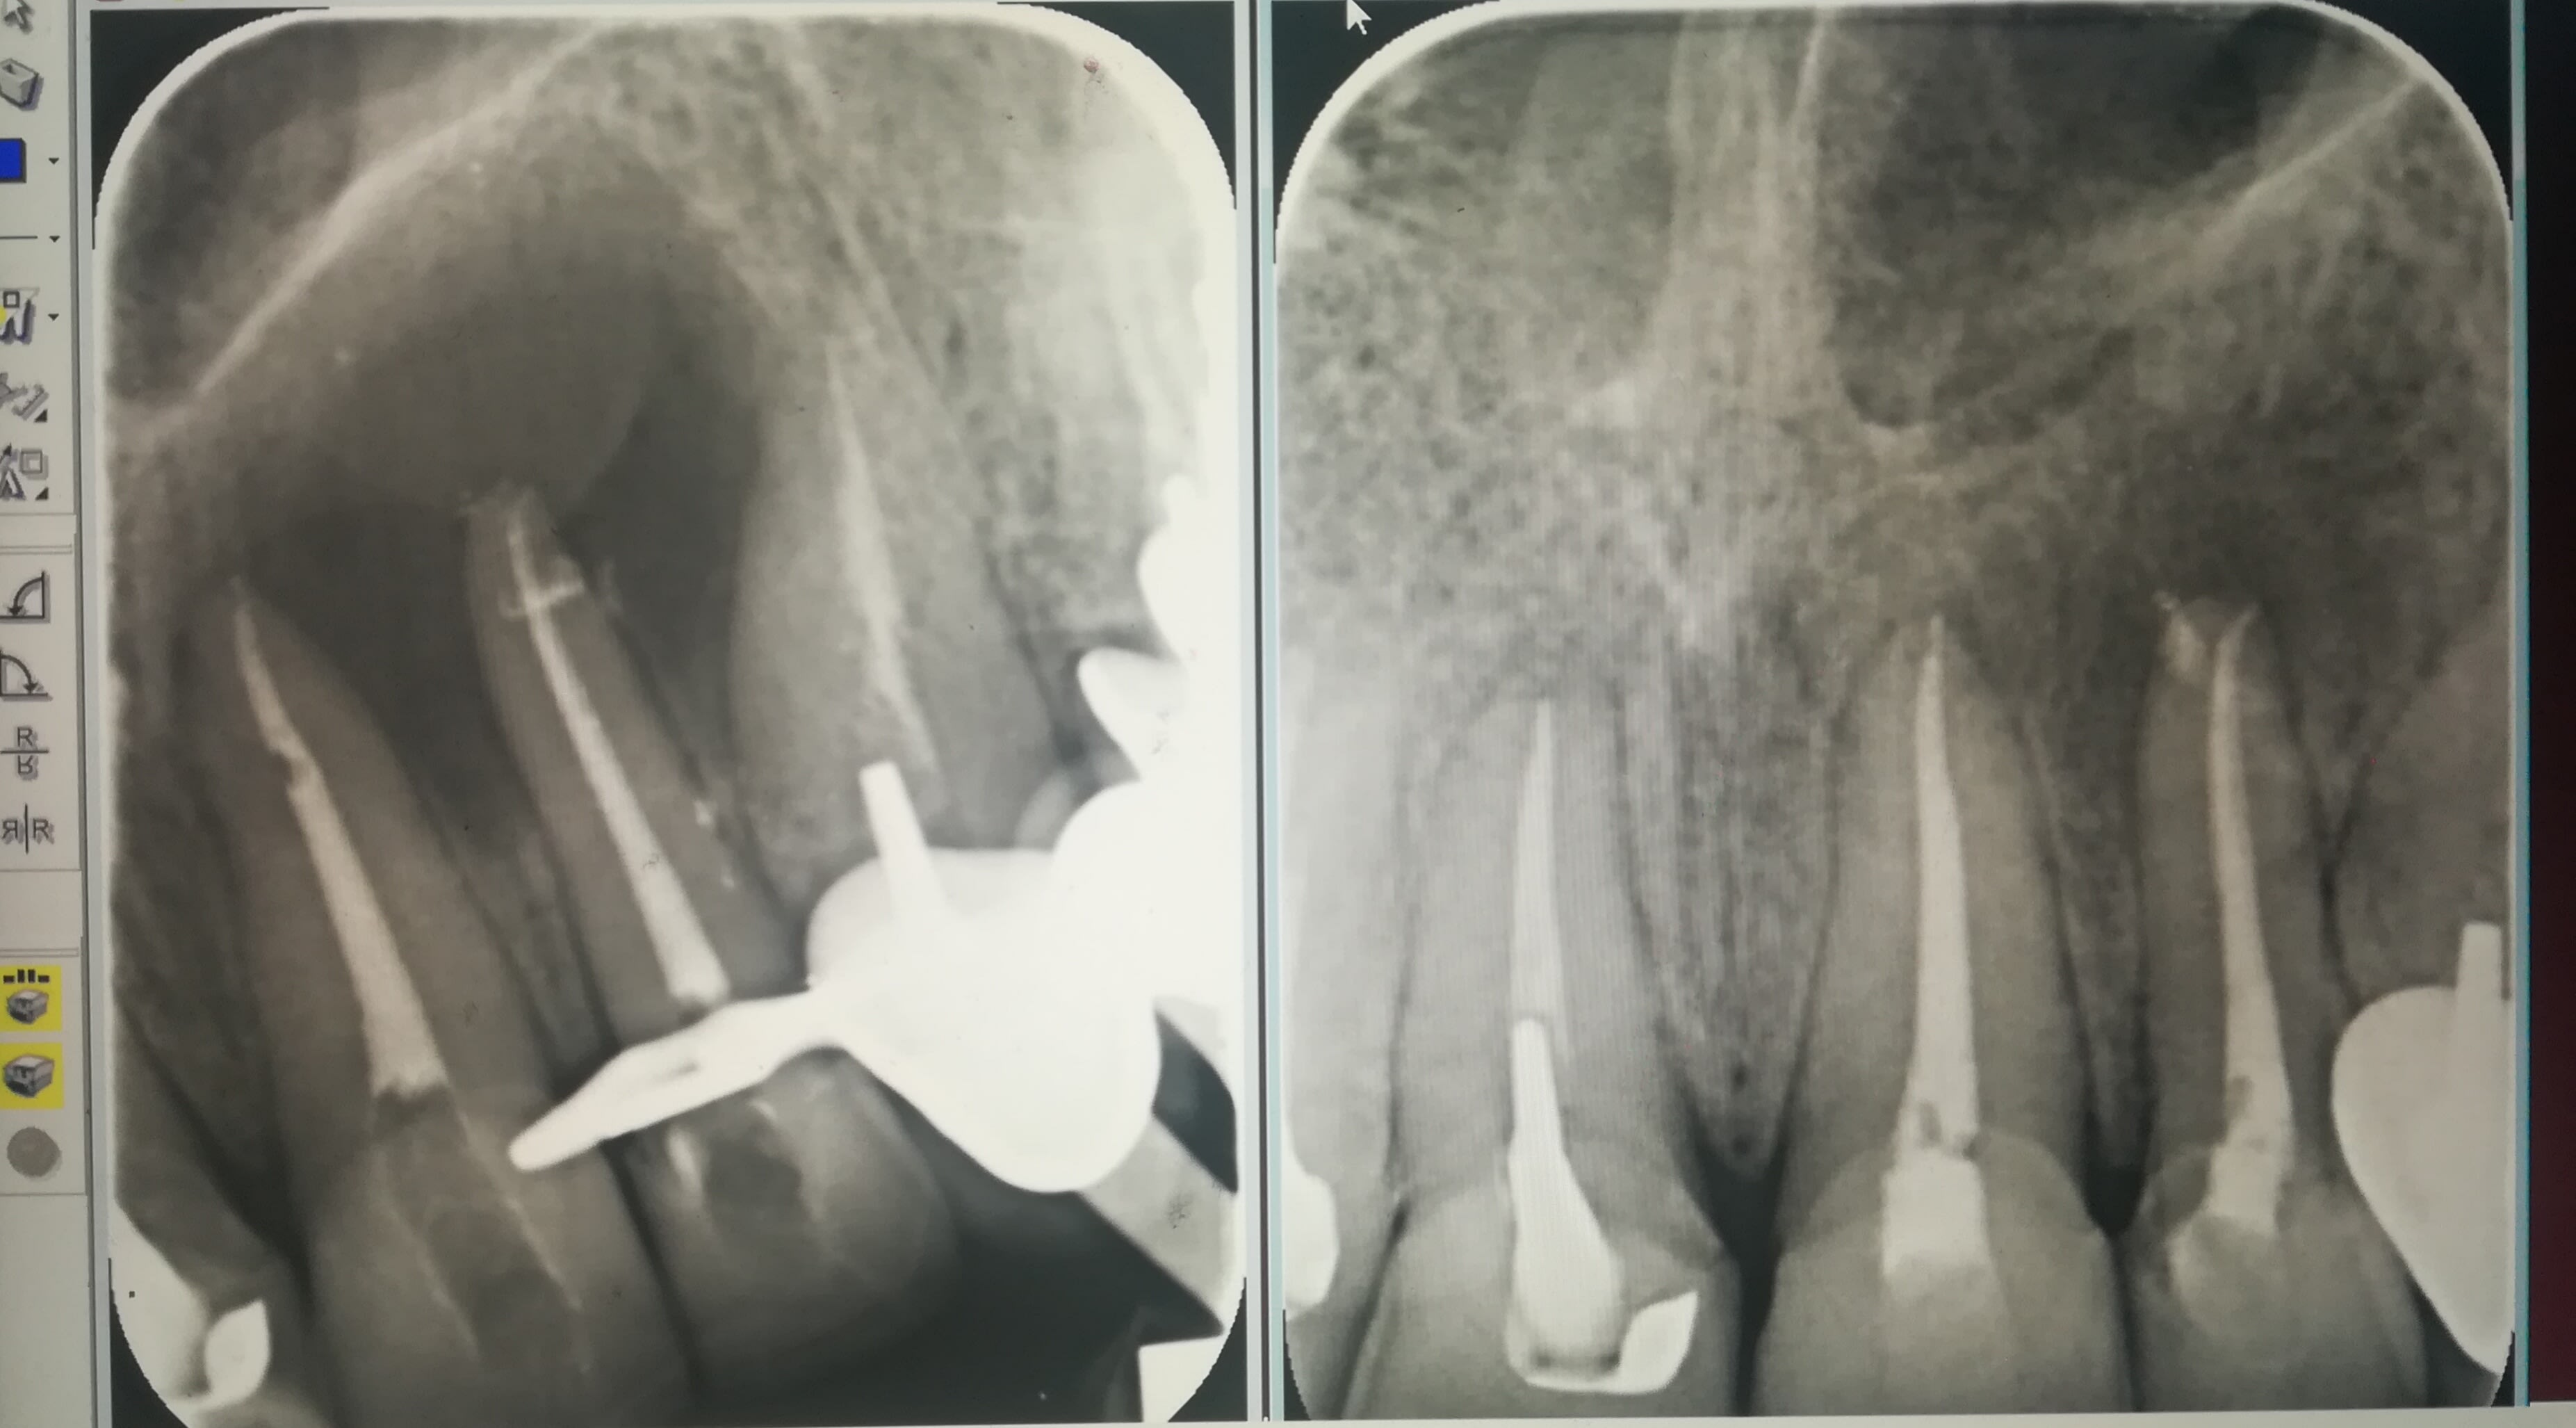

Je partage ici un cas d'un patient adressé pr résections apicales:

Endos de merde avec des couronnes impeccables et des inlay cores (dont l'intérêt est uniquement ds la facture:comme celui de la 11...)

Tuméfaction palatine volumineuse et douleurs nécessitant des codéines.

J'ai pris la décision de tenter de déposer ces IC à travers les ccc et retraiter avant de penser à la chir. +incision et drainage de la collection au palais.

C'était en juin, et voici le contrôle :a gauche le jour de rte, à droite aujourd'hui

C est tres propre et tres rapide comme cicatrisation.